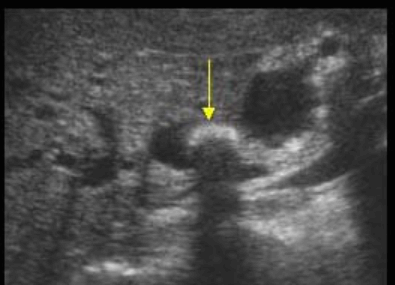

Choledocholithiasis US finding

- 총담관 내에 후방음향음영을 동반한 강한 에코가 관찰된다.

- 총담관의 확장 소견이 보인다. ( 7mm 이상)

- 담석이 관찰되지 않고 간외, 간내담관의 확장소견을 시사하는 엽총징후(shotgun sign)이나 평행관 징후(parallel channel sign)가 관찰되기도 한다.

- 엽총징후(shotgun sign): 간외 담관이 확장되어 간외 담관과 문맥이 이웃해 관찰된다.

- 평행관 징후(parallel channel sign): 간내 담관이 확장되어 인접하고 있는 문맥과 나란히 2개의 관상구조로 나타난다.